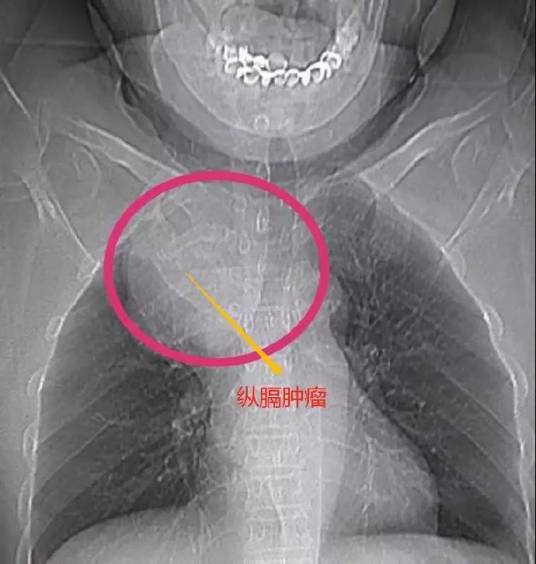

后纵隔肿瘤

是一组起源于纵隔的肿瘤,包括胸腺瘤、胸内甲状腺肿、支气管囊肿、皮样囊肿、畸胎瘤、淋巴肉瘤、恶性淋巴瘤、心包囊肿、脂肪瘤、神经源性肿瘤、食管囊肿等,以良性者居多。畸胎瘤多见于30岁以下,其余均多发生在40岁以上。本病除淋巴肉瘤和恶性淋巴瘤多数预后良好。